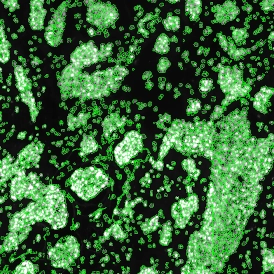

Immunofluorescence image analysis, as part of tissue cytometry, is an excellent method for understanding many immune changes and profiling tumor microenvironments. 2 The workflow starts with sample preparation and staining of the target(s) of interest in cultured cells or tissue sections. Then, automated fluorescence whole-slide imaging can be performed and image analysis to detect nuclei or phenotypes can begin.

One of the great strengths of this method is that the technique can be multiplexed to examine multiple targets in the same tissue/experiment. This means the introduction of multiple markers onto a single tissue sample, typically emitting at different wavelengths so they can still be distinguished from each other, as well as multiple staining/imaging rounds ( CycIF ). While the use of multiplexing does introduce additional complexity into data analysis workflows, using automated imaging and analysis makes it possible to perform multiparametric analysis of a tissue section simultaneously. 3

Some of the key challenges, particularly for multiplexed data sets, are dealing with large data sets, discovering automated ways to reconstruct images, finding computationally efficient ways to perform image segmentation, and trying to perform these immunofluorescence image analysis tasks in a standardized way. Other challenges concern the experimental protocols, optimization, spectral overlap, and finding the appropriate antibodies.